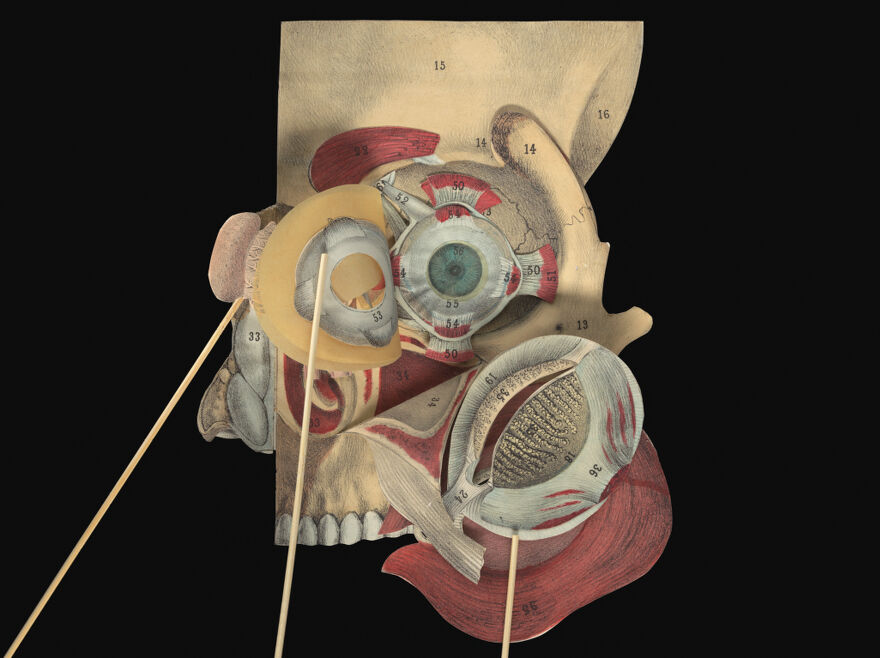

A pictorial manikin, or, Movable atlas / by Professor G.J. Witkowski.

- Witkowski, G.-J. (Gustave Joseph), 1844-1923. Anatomie iconoclastique. English

Credit: A pictorial manikin, or, Movable atlas / by Professor G.J. Witkowski. Source: Wellcome Collection.